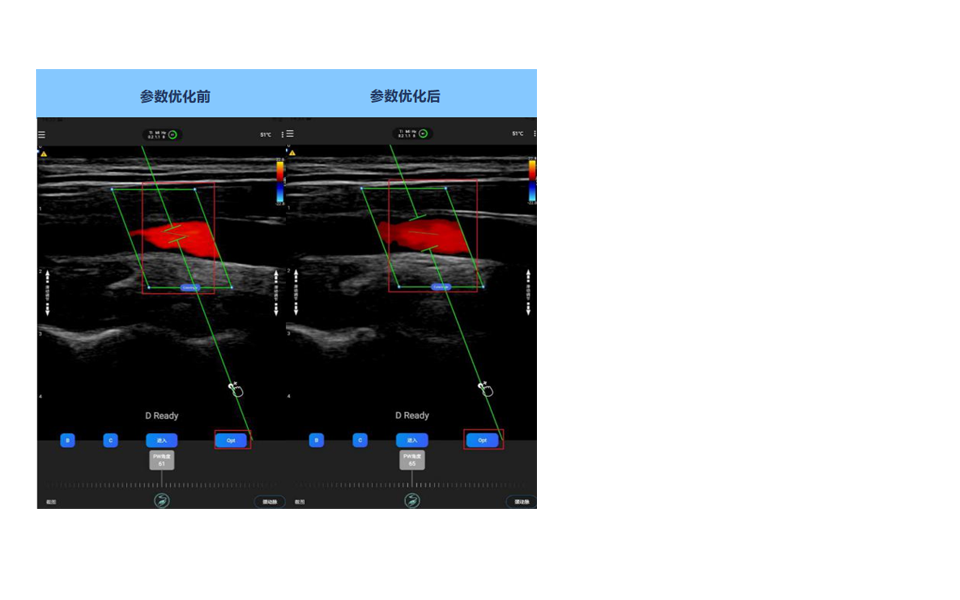

D模式模式角度、位置、采样容积AI自动一键优化调节

技术特点

进入D-ready模式时,AI会自动找到最佳D模式入射角度,采样门(Gate)的最佳位置,以及修正角度(Steer Angle)。 如果调整了的血管的位置与角度,点击 Opt一键优化按键, AI会自动调整Dready 模式下,采样门位置以及修正角度,帮助用户计算准确的血流速度。

如果需要进入流量计算,请在当前切面下保持,多次点击Opt 一键优化按键,则AI会默认在流量计算与普通速度计算之间进行切换,改变采样门大小,从全部血管大小改变为默认采样门大小。

注意,流量测量必须使用采样门为全部血管大小,如左中间图所示;不佳的血流角度(超过60°),会引起测量误差。